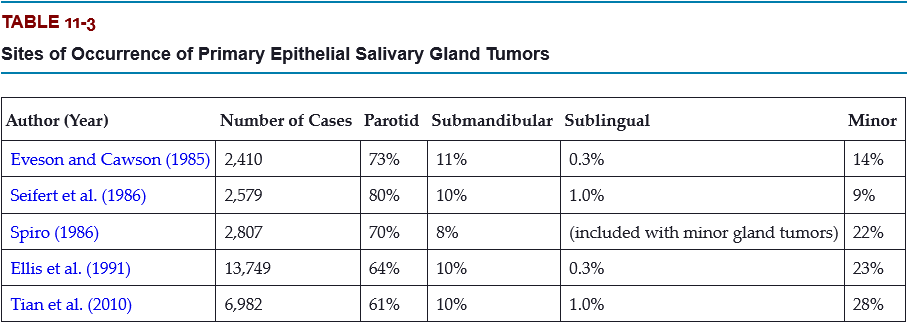

What is the most common site for salivary gland tumors?

- parotid gland

- submandibular gland

- sublingual gland

- minor glands

A. parotid gland

The most common site for salivary gland tumors is the parotid gland, accounting for 61% to 80% of all cases.